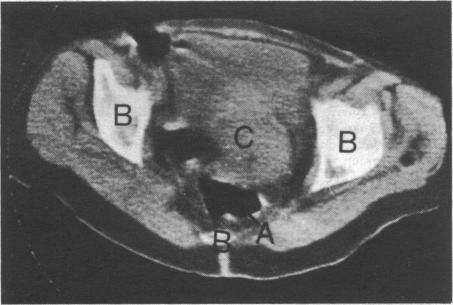

Sheep IgG antibody to carcinoembryonic antigen (CEA) was radiolabelled with 131I and used to identify human gastrointestinal tumours by external subtraction imaging. 99Tc-pertechnetate and 99Tc-human serum albumin were used to identify tissue spaces. In 13 patients with tumours four out of five primary sites and eight out of 11 secondary sites were successfully shown. Two patients with benign disease had negative scans. Comparison with conventional methods of scanning showed good correlation. The success of this pilot study should encourage the search for more tumour-specific antigens and further study of the implications for treatment.

用131I对癌胚抗原(CEA)的绵羊IgG抗体进行放射性标记,并通过体外减影成像用于识别人类胃肠道肿瘤。用99Tc-高锝酸盐和99Tc-人血清白蛋白来识别组织间隙。在13例肿瘤患者中,5个原发部位中的4个和11个继发部位中的8个被成功显示。2例良性疾病患者扫描结果为阴性。与传统扫描方法的比较显示出良好的相关性。这项初步研究的成功应鼓励寻找更多肿瘤特异性抗原,并进一步研究其对治疗的意义。